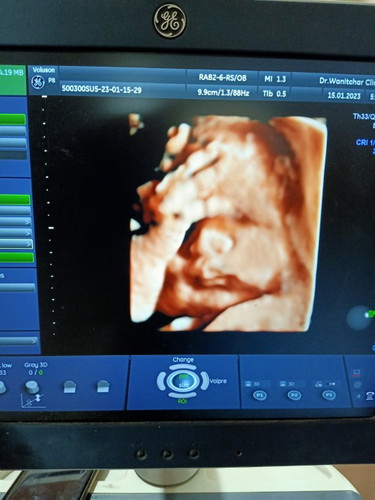

29+3week ลูกชายหนัก2.0โล ปกติต้อง1.1-1.2 คุณหมอบอกเกินเกณฑ์ไปมากท้องแรกก็ผ่าคลอด